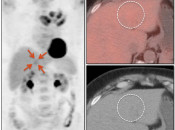

- Particularly useful in identifying very subtle liver lesions that may be missed on the axial images. [Case 2] [Case 3] [Case 4]

- Case 706: 1 subtle lesion, barely seen.

Quick MIP!

Axial CT 103 (nothing seen)

Axial Fused 103 – subtle FDG lesion right liver! - Case 705: 1 subtle lesion.